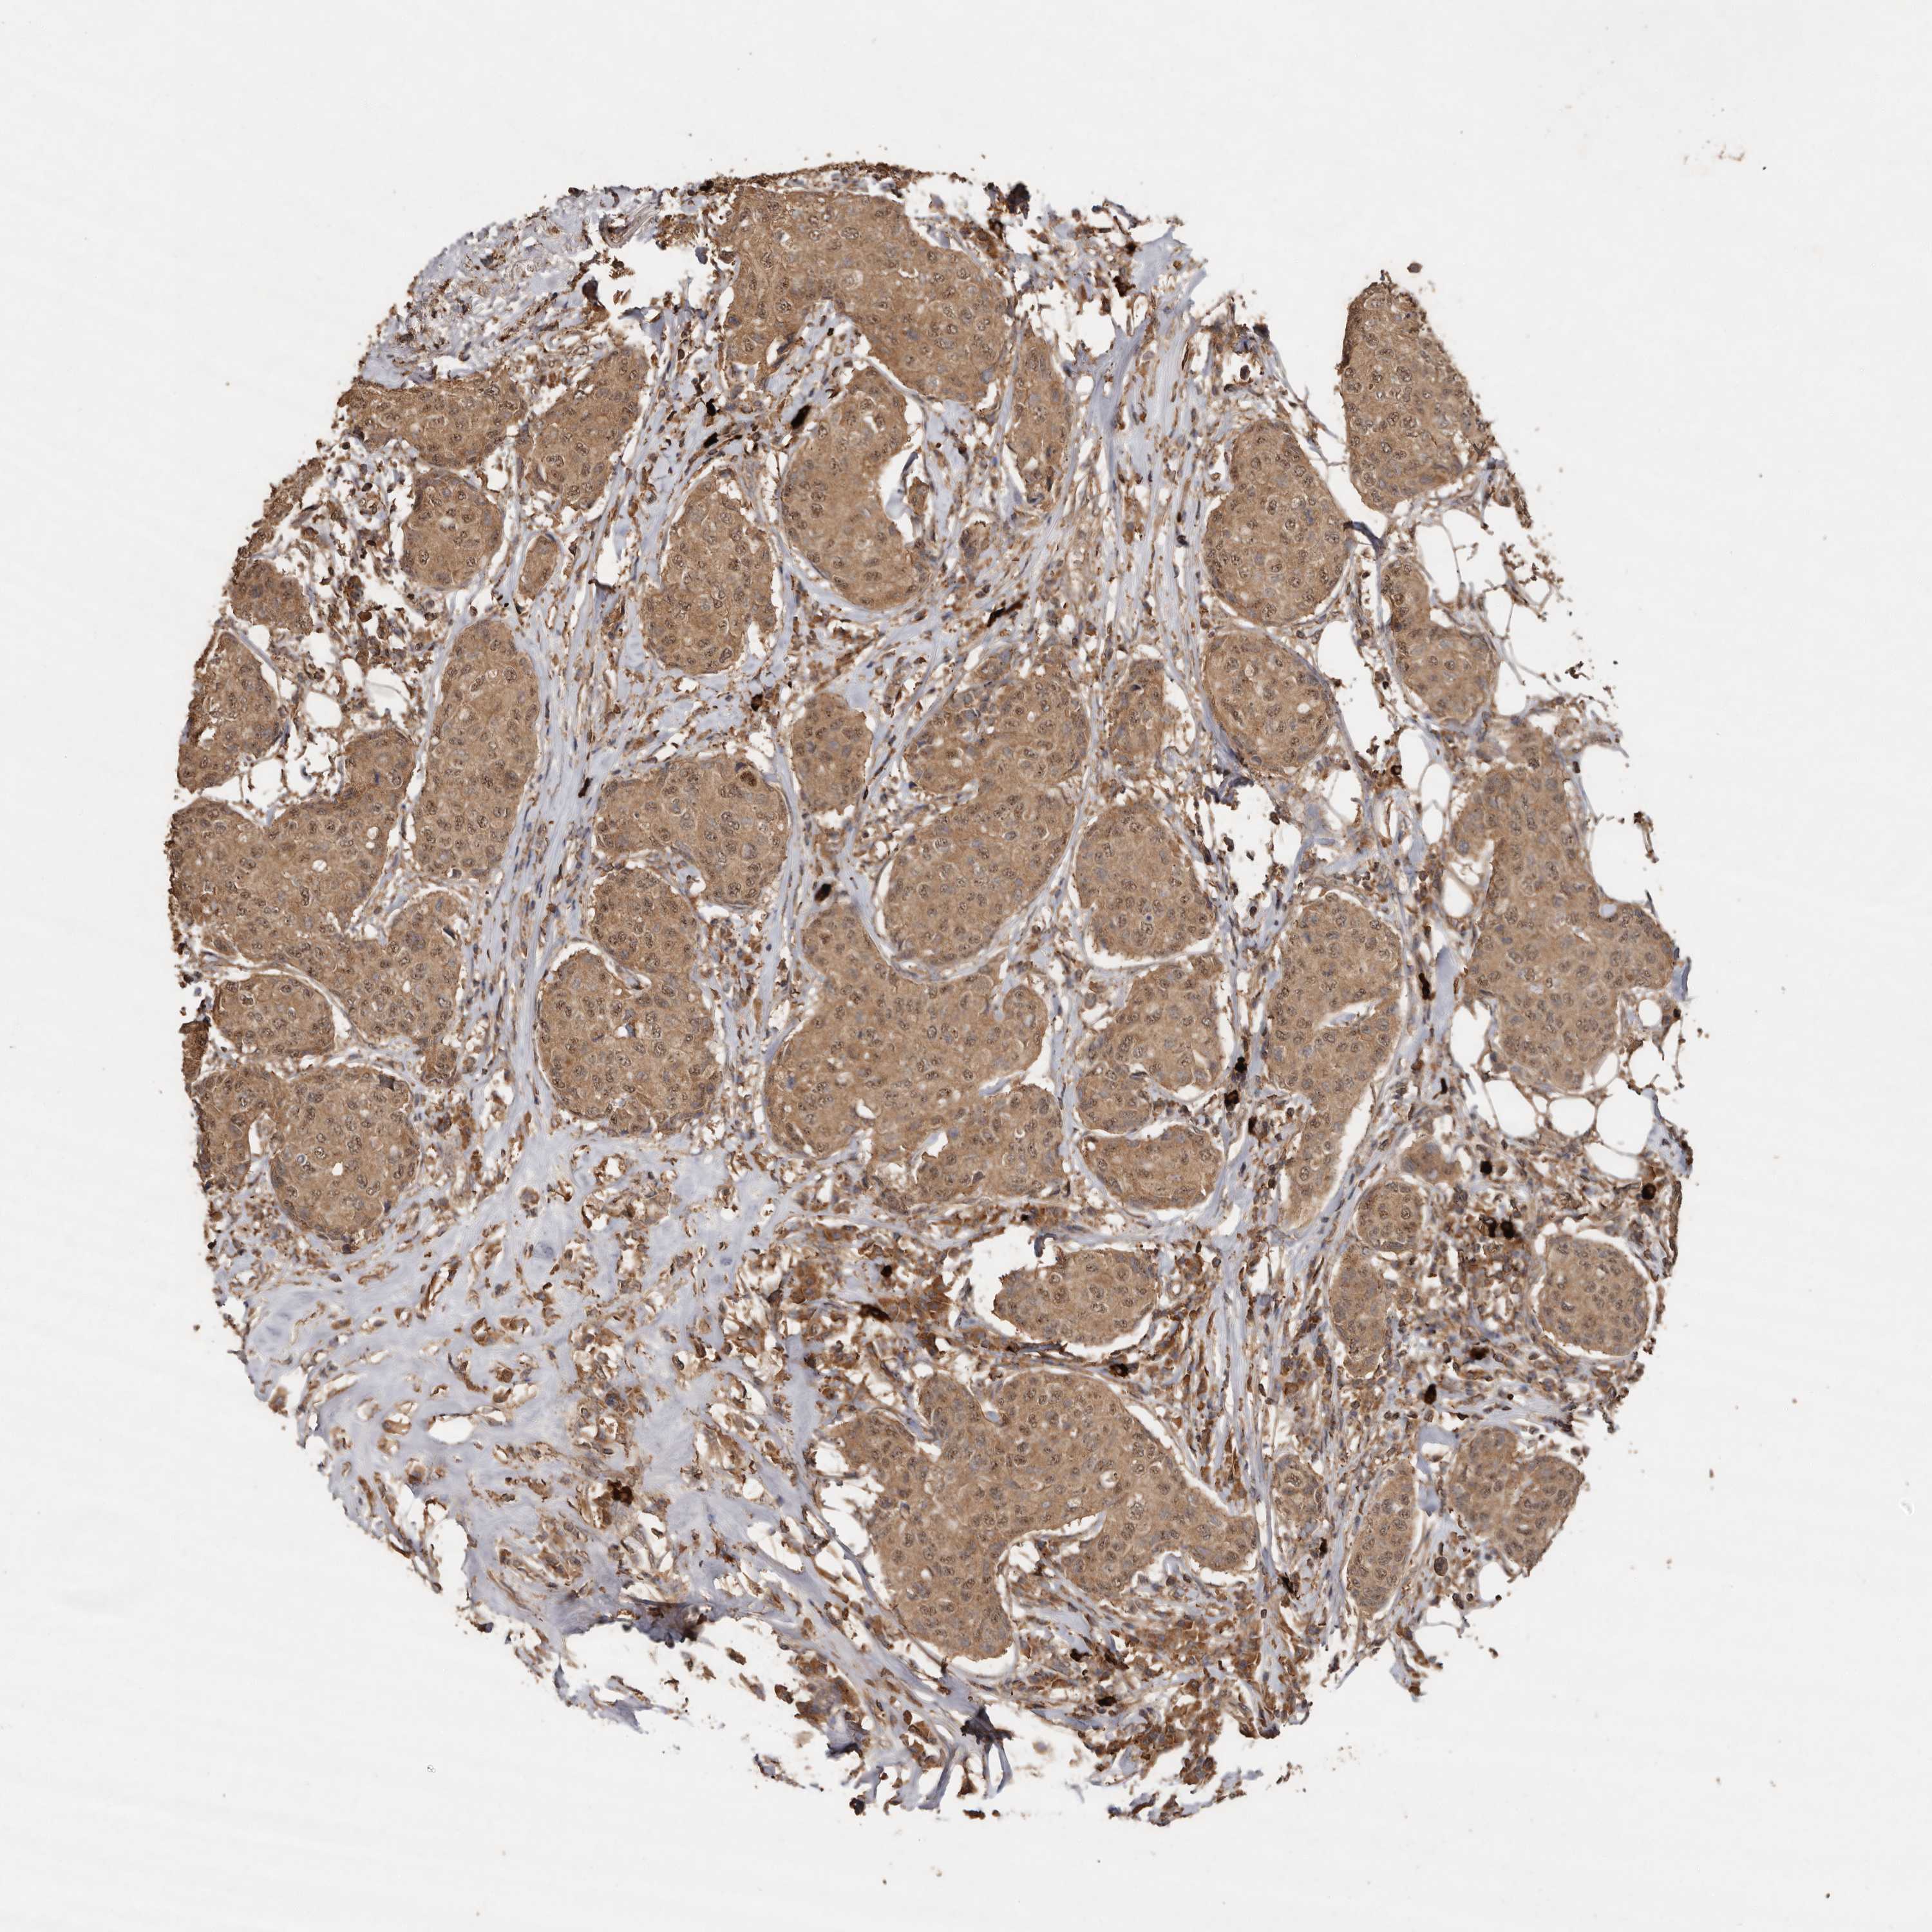

CANCER BREAST CANCER Show tissue menu

BRCA TCGA BRCA VALIDATION PROTEIN EXPRESSION